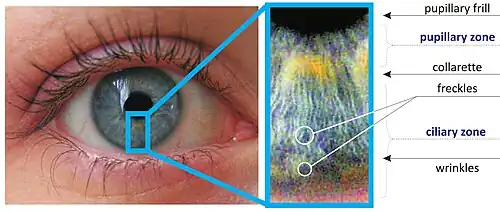

The iris is divided into two major regions:

- The pupillary zone is the inner region whose edge forms the boundary of the pupil.

- The ciliary zone is the rest of the iris that extends to its origin at the ciliary body.

The collarette is the thickest region of the iris, separating the pupillary portion from the ciliary portion. The collarette is a vestige of the coating of the embryonic pupil.[3] It is typically defined as the region where the sphincter muscle and dilator muscle overlap. Radial ridges extend from the periphery to the pupillary zone, to supply the iris with blood vessels. The root of the iris is the thinnest and most peripheral.[4]

- The crypts of Fuchs are a series of openings located on either side of the collarette that allow the stroma and deeper iris tissues to be bathed in aqueous humor. Collagen trabeculae that surround the border of the crypts can be seen in blue irises.

- The midway between the collarette and the origin of the iris: These folds result from changes in the surface of the iris as it dilates.

- Crypts on the base of the iris are additional openings that can be observed close to the outermost part of the ciliary portion of the iris.[4]